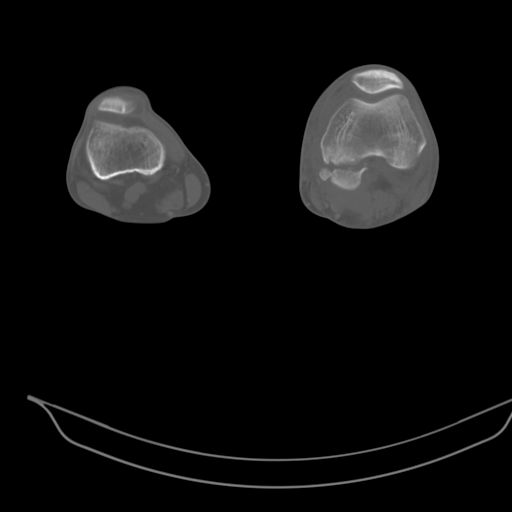

При внутрисуcтавных переломах трехмерные (3D) изображения, кроме красивого снимка, не дают полную информацию о состоянии отломков, самыми информативными являются корональные срезы на КТ и обычная длинная ренгенограмма конечности для сравнения оси конечности.

Фронтальные внутрисуставные переломы мыщельков бедра, так называемые Hoffa fracture, не частые, но встречающиеся переломы, в основном они связаны с травмой высокой энергией.

В зависимости от смещения рекомендуется сопоставление костных фрагментов с последующей жесткой фиксацией.

В вашем случае доступ будет медиальный, сопоставить развернутый медиальный мыщелок и фиксацию надо произвести в передне-заднем

направлении шурупами 4.5 мм в диаметре, углубив головку шурупов под хрящ, а поперечную фиксацию - межмыщелковыми шурупами. Желательно применить шурупы 6.3 мм в диаметре. Дополнительная Buttress technique пластина предотвратит перелом от скольжения.

Даже при сросшемся переломе мыщелка рекомендуется реконструктивная операция для предотвращения последующих варус или вальгус деформации.

Место образовавшего костного дефекта после разворота мышелка заполняется спонгиозной аутокостью. Костная пластика применяется даже

в свежем случае.

Под наркозом редрессация, ранняя разработка сустава после операции, нагрузка на конечность через 12 недель помогут удержать без коллапса

фиксацию и поможет больному восстановить функции конечности без артропластики коленного сутава.